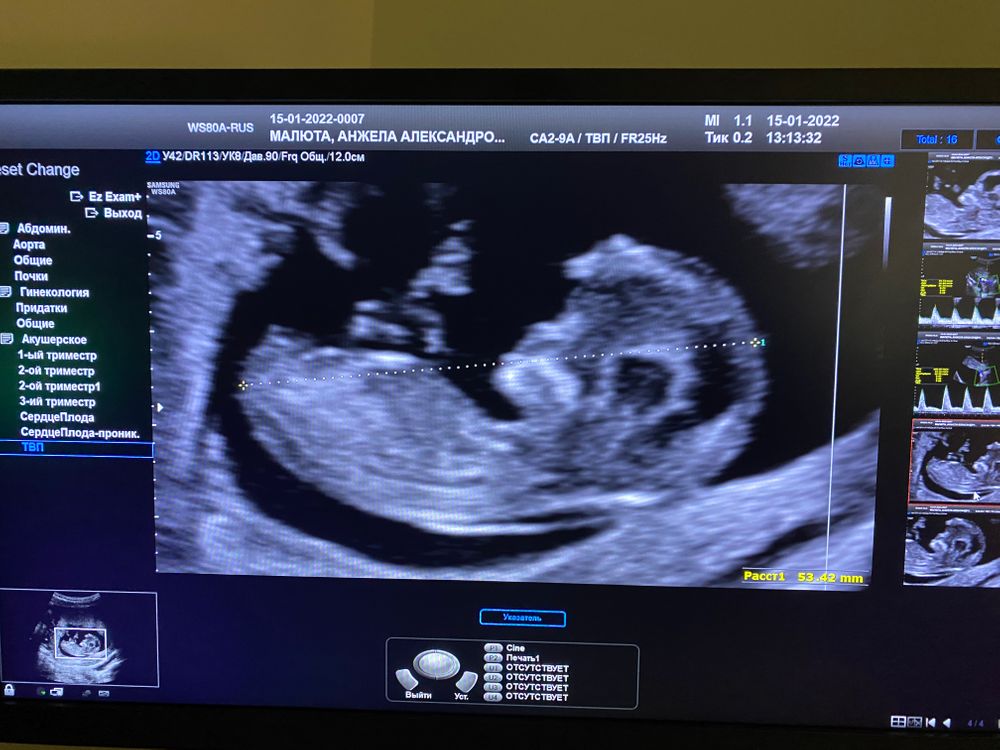

Вот ещё))